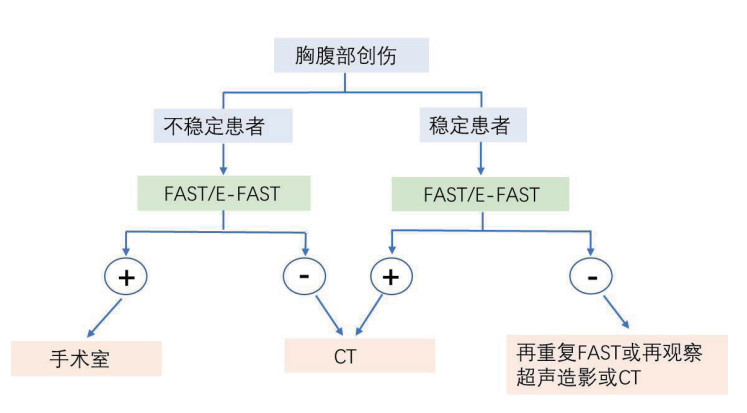

2.5 腹部超声胸腹腔出现游离液体往往是器官损伤的标志,创伤重点超声评估(FAST)对于腹腔积液有较高的准确性,特别是病情不稳定闭合性腹部损伤。既往前瞻性研究发现在772例患者进行FAST评估,对于病情相对不稳定患者,有29%(15/52)FAST为阳性者存在腹腔内的隐匿性损伤[44],故对可疑病例应进行早期FAST伤情评估,并根据结果来提前预判下一步诊疗方案(图 9)。

|

| 图 9 对行FAST评估的创伤患者的诊断流程 |

|

|